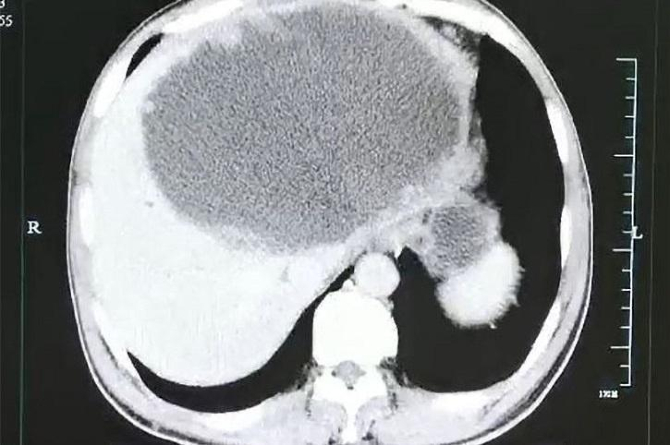

डॉक्टरांनी या व्यक्तीचे सीटीस्कॅन रिपोर्ट पाहिजे तेव्हा त्यांना धक्काच बसला. या व्यक्तीच्या यकृताचा डावा भागामध्ये मोठ्या प्रमाणात पू झाला होता. तसेच या भागामध्ये त्यांना १९ सेंटीमीटर लांब आणि १८ सेंटीमीटर रुंदीच्या अळी आढळल्या. तसेच या व्यक्तीच्या यकृतामध्ये ट्युमर्सही आढळून आले. या व्यक्तीच्या बऱ्याच आरोग्य चाचण्या करण्यात आल्यानंतर परजीवी अळ्यांमुळे होणाऱ्या आजारामुळेच त्याला त्रास होत असल्याचे स्पष्ट झालं.

Photo : AsiaWire / Hangzhou 1st Hospital